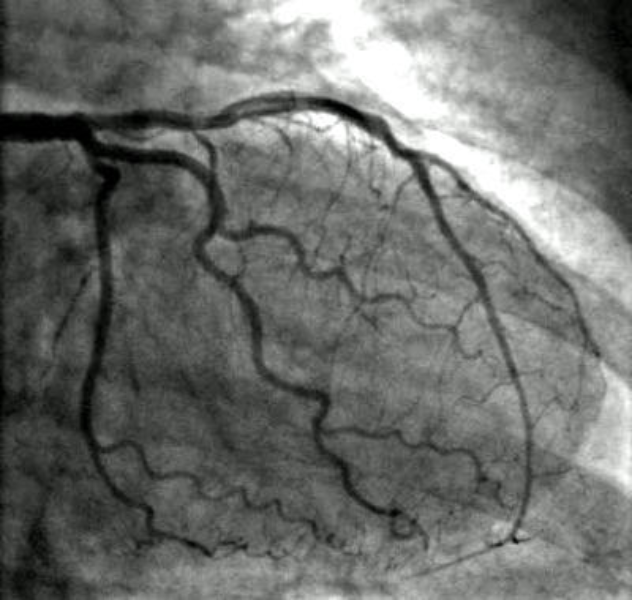

Angiogram Test in Bangalore for Precise Heart Diagnosis

An angiogram test is a crucial procedure for assessing the health of your heart’s blood vessels. When experiencing symptoms like chest pain, breathlessness, or unexplained fatigue, it’s essential to have a detailed understanding of your heart’s condition. In Bangalore, Dr. Kumar Kenchappa offers the angiogram procedure to help patients get a clear picture of their heart health. The test uses a special dye and imaging technique to show how blood flows through the arteries, revealing any blockages or narrowing that could affect heart function.

For many, the angiogram is a turning point transforming uncertainty into clarity. Once blockages are identified, doctors can recommend the best treatment options, whether it’s lifestyle changes, medications, or procedures like angioplasty. Most patients are surprised by how simple the procedure is and how quickly it provides the answers they need.